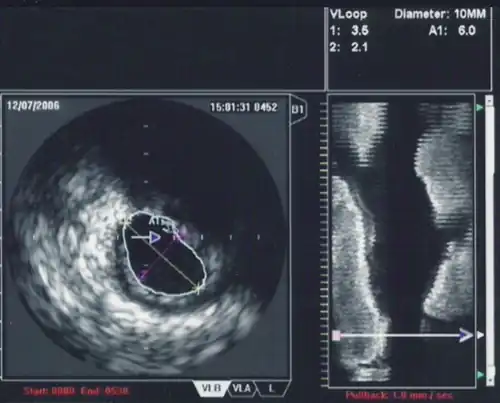

Intravascular ultrasound, also known as a percutaneous echocardiogram is an imaging methodology using specially designed, long, thin, complex manufactured catheters attached to computerized ultrasound equipment to visualize the lumen and the interior wall of blood vessels.